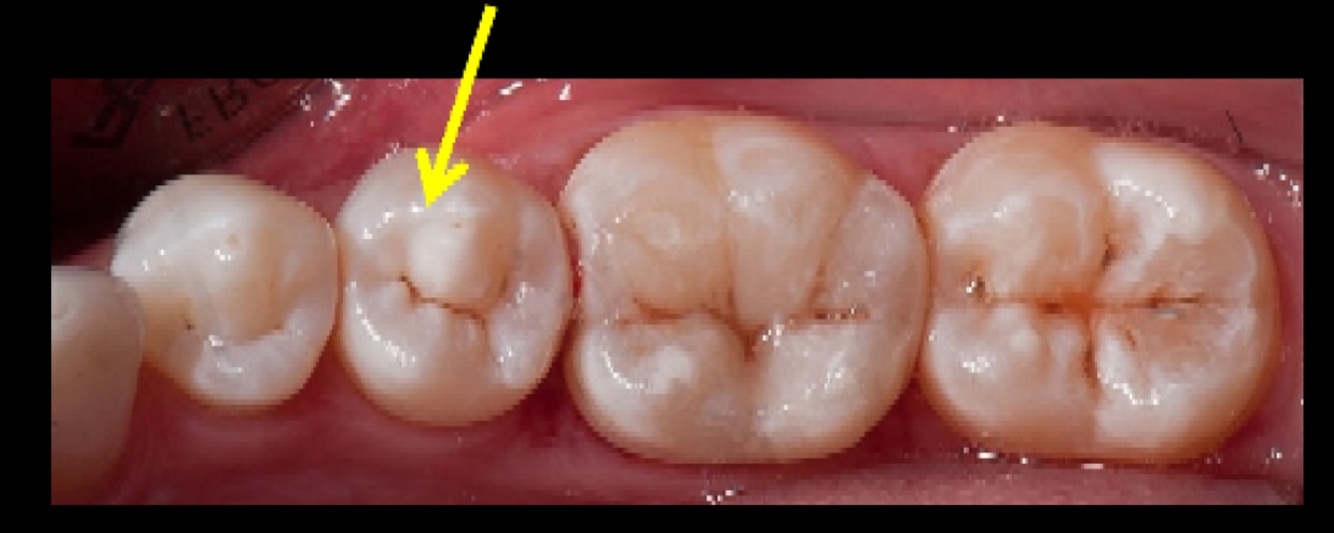

18

Q

Identify the restored tooth using both the long-hand and FDI notation systems:

19

Which tooth was mistakenly recommended for extraction?

Referral “Dear Oral Surgeon, Please extract the unrestorable remaining roots: 17, 14, 26,”